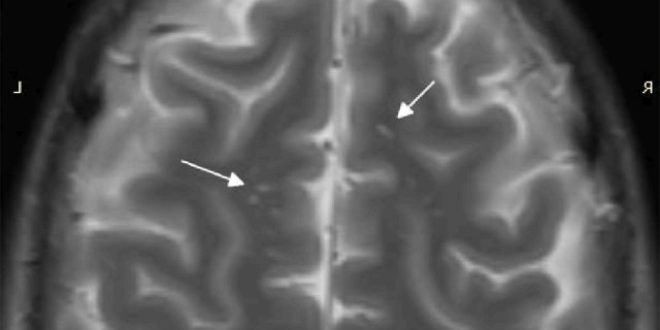

Мрт головного мозга глиоз или РС

Очаги глиоза в головном мозге в белом веществе (единичные) на МРТ: что это такое? Нервная система – основа полноценной жизни и осуществления рефлекторной деятельности человека. При ее поражении…